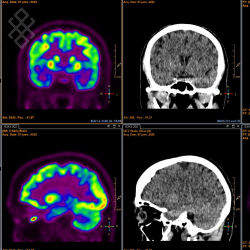

Tomoscintigraphie Cérébrale

Pour une CERETEC, il y a 3 étapes. Premièrement, on vous posera une voie veineuse et vous devrez rester pendant 30 minutes au calme dans le noir. Deuxièmement, vous recevrez une injection du produit radioactif et vous devrez rester pendant 30 minutes au repos dans le noir. Troisièmement, on vous installera dans le support tête pour l'acquisition qui durera environ 60 minutes. Pour un DATSCAN, il y a 4 étapes. Premièrement, pour saturer la thyroïde, on vous donnera 5 gouttes de Lugol et vous devrez attendre 30 minutes. Deuxièmement, vous recevrez une injection lente du produit radiopharmaceutique et vous devrez attendre 3 heures. Troisièmement, avant de vous installer dans le support tête, vous devrez boire un verre d'eau. Quatrièmement, le manipulateur en radiologie effectuera l'acquisition pendant environ 1 heure.